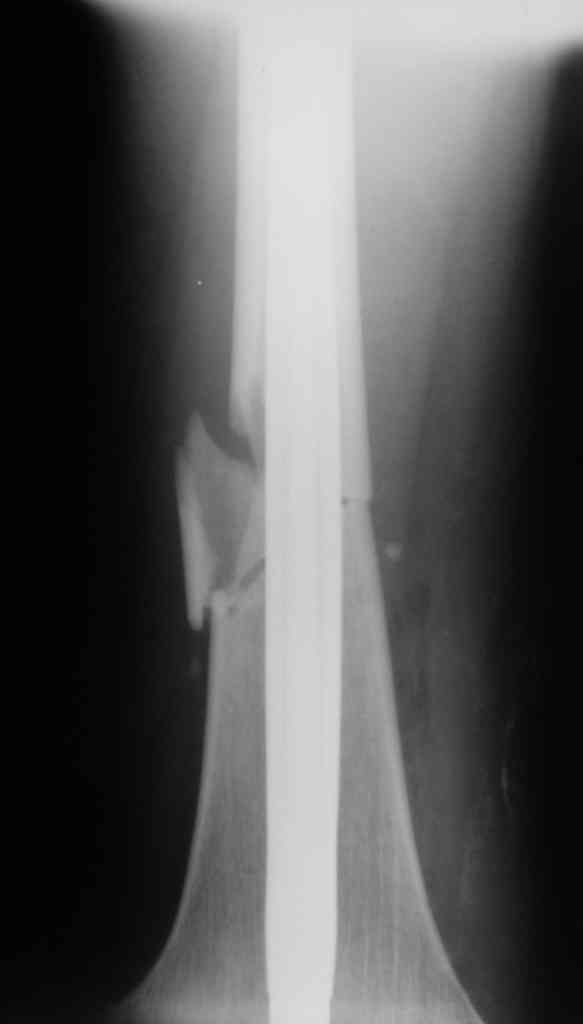

Дорогой Александр. Имею скромный опыт использования системы Fixion при переломах плеча, бедра и тибии. Всего 18 наблюдений с сентября 2006 г. Результаты отличные. Гвоздь индивидуален для каждого медуллярного канала. Легко имплантируется как в узкий, так и в деформированный канал. Это позволяет применять метод интрамедулярного остеосинтеза без ненужных потерь времени операции, флюороскопии и реально снижает крвопотерю и операционный риск. Удаление происходит без проблем. Особенно интересны больные с ипсилатеральными переломами бедра и голени.

В отношении ранней нагрузки при спиральных переломах лучше не торопиться. По данному случаю необходимо достигнуть исчезновения щели между штифтом и внутреним кортексом по Rg. А так картинка прекрасная - и длина сегмента и репозиция. Можно поздравить, коллега!

Да, спасибо за интересные иллюстрации. Получилось очень симпатично. На большеберцовой кости непременно надо было винты? Там же был торцовый упор, перелом в средней трети?